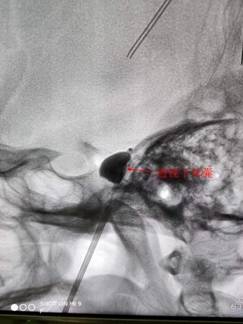

三叉神经球囊压迫术是一种微创治疗,手术基本方法为从面部皮肤穿刺达到三叉神经出颅腔的部位,以球囊导管置入麦克氏囊,通过球囊扩张适度压迫三叉神经半月节,目的是卡压三叉神经的痛觉纤维并最大程度保留触觉纤维的功能。

为了治病,季阿婆子女带着她四处求医,尝试过三叉神经射频手术没有效果,开颅行微血管减压手术又因年龄太高危险太大而止步。四处打听,他们来到我院神经外科门诊求医。针对老人的病情,专家团队为老人施以“三叉神经球囊压迫术”治疗。术后,老人反馈疼痛症状已经消失,医生也告知以后不再需要服用药物,她终于愁眉舒展,喜笑颜开。